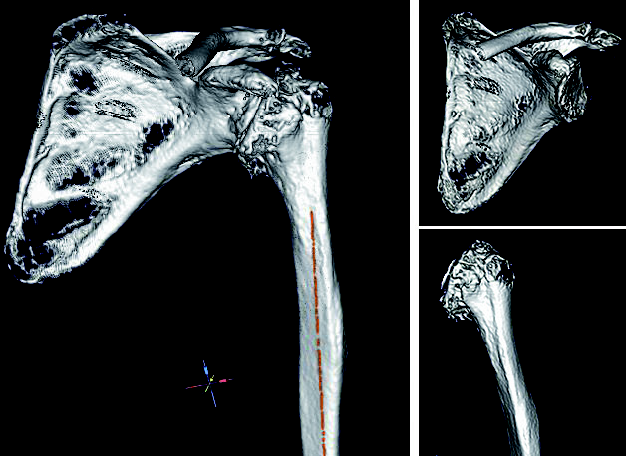

even a 3D plan. However, 3D planning is based on CT images, and unfortunately I do not always have a suitable CT with the appropriate thin-slice resolution and dimensions (entire scapula and epicondyles), because many patients only have an MRI with them, which usually does not show the end points of the affected bones that are actually required, and they assume that this is sufficient.

and assume that this is sufficient. However, digital 2D planning is also possible on the basis of an

MRI, but with significantly more limited information than 3D planning with reproducible reference planes in the scapula planes and humeral axes.

The automatic bone segmentation

Another advantage of mediCAD® Shoulder 3D is that the surgeon himself (and not some engineer of the implant manufacturer) can perform the segmentation of the CT data set according to his medical experience and interpretation of the CT images. In addition, the creation of a 3D model and the possibility of subsequent planning of the glenoid and humerus individually one after the other are possible. Also, full joint planning after reduction of the joint with implanted components are features that I, as a physician, would not want to miss. And of course the 3D ROM analysis of the reduced joint with the prosthesis in place.